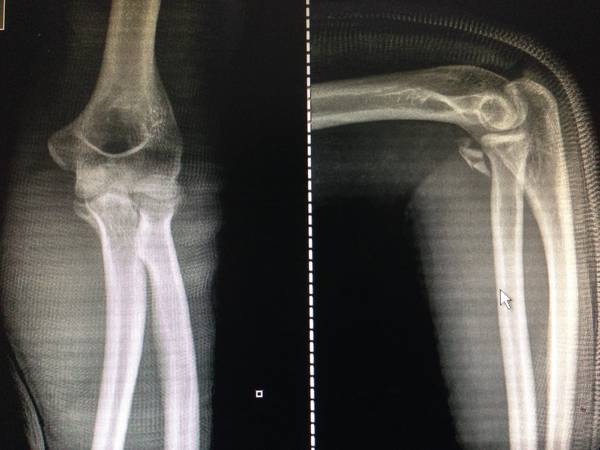

选择哪个部位手术入路